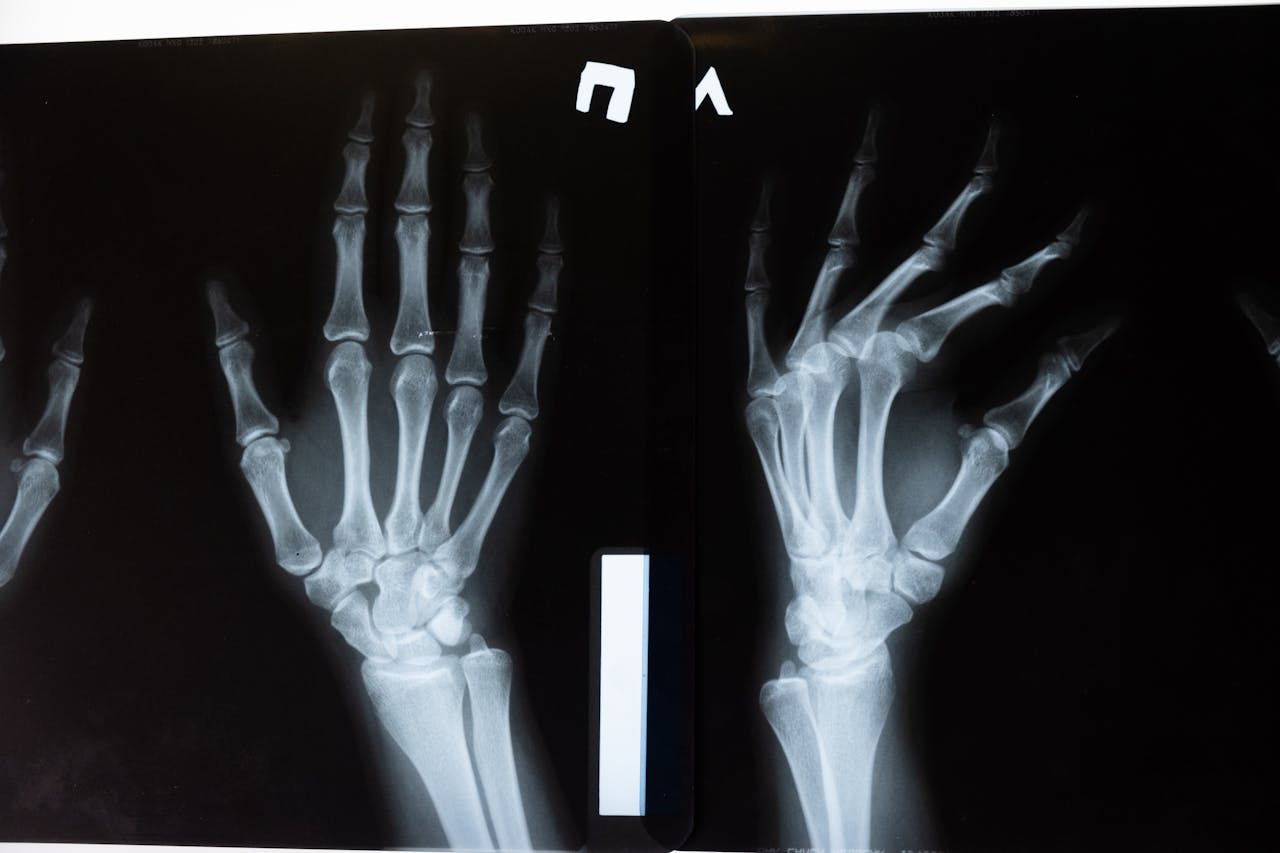

En una investigación judicial, la historia clínica es una prueba central. Es el registro legal de lo actuado, observado, prescrito y ejecutado. Una historia clínica incompleta, desordenada, sin firma o sin coherencia cronológica puede ser interpretada como negligencia, aunque la atención haya sido adecuada.